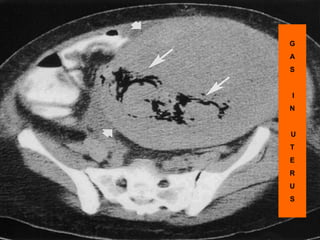

G

A

S

I

N

U

T

E

R